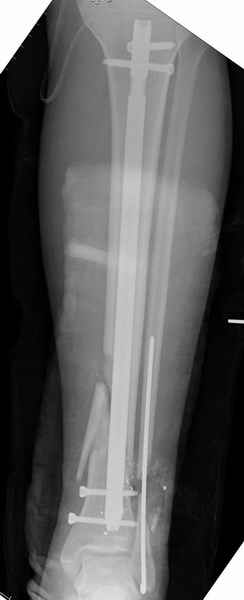

На снимках варианты фиксации малоберцовой:

№ 1 двух лодыжек

№ 2-5 при огнестрельном переломе

№ 6-11 при pilon percutaneus fixation